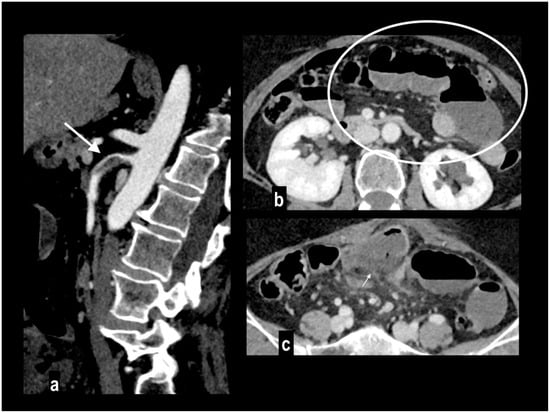

4.2. Bowel Findings

Immediately after acute arterial obstruction, the bowel shows a spastic reflexus ileus (gasless abdomen in plain X-ray), followed by hypotonia (hypotonic reflexus ileus) and parietal thinning (paper-thin sign) [38]. At CT, the bowel wall appears thinned (paper-thin) with decreased or absent parietal enhancement [2,49]. These findings are extremely specific for the diagnosis (up to 97–99%) [30,33], but they may be not evident in the early stage of the disease in which an accurate analysis of vessels should be carried out (Figure 8).

Figure 8.

Acute abdominal pain in a 66-year-old woman. Atheromasic low-density plaque at the proximal SMA with luminal stenosis ((a) arrow). Dilated paper-thin small intestine wall ((b) circle). Segmentary transmural necrosis was observed on the mesenteric side of an intestinal loop (arrow), intestinal wall line loss and periparietal fluid effusion (c). The patient underwent surgical resection of the necrotic loop.

The comparison of parietal enhancement between an affected and a normal bowel in the arterial phase, particularly in segmentary ischemia, is extremely useful for the diagnosis [17].